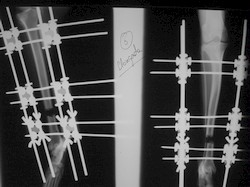

PRÁCTICAS CURSO DE FIJACIÓN EXTERNA PERFECCIONAMIENTO.

Elongacion.